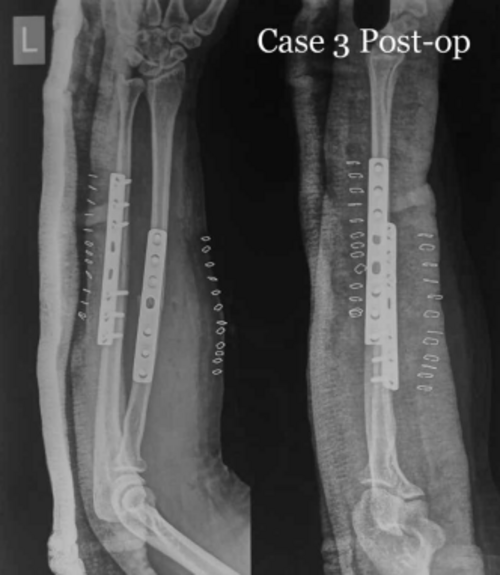

Successful Management of Midshaft Radius and Ulna Fracture - Dr. Rahul Jagtap

Dr. Rahul Jagtap, an Orthopedic Surgeon based in Navi Mumbai, successfully treated a 35-year-old female patient who presented with a midshaft radius a...